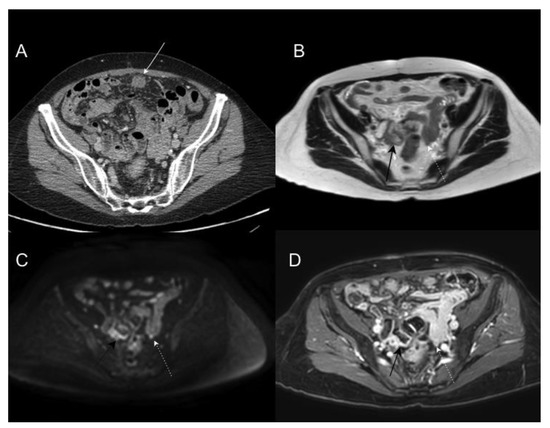

- Kim, S.H.; Choi, Y.H.; Kim, J.W.; Oh, S.; Lee, S.; Kim, B.G.; Lee, K.L. Clinical significance of computed tomography-detected ascites in gastric cancer patients with peritoneal metastases. Medicine 2018, 97, e9343. [Google Scholar] [CrossRef] [PubMed]

- Zheng, L.-N.; Wen, F.; Xu, P.; Zhang, S. Prognostic significance of malignant ascites in gastric cancer patients with peritoneal metastasis: A systemic review and meta-analysis. World J. Clin. Cases 2019, 7, 3247–3258. [Google Scholar] [CrossRef] [PubMed]